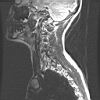

CWZ